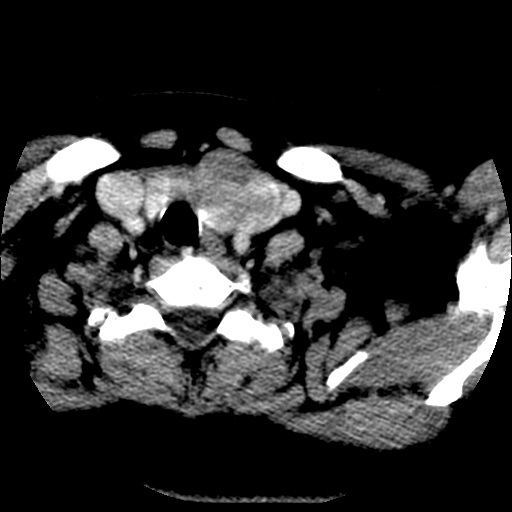

标题: CT25491:女,55岁,发现左侧甲状腺肿块一个月。 [打印本页]

标题: CT25491:女,55岁,发现左侧甲状腺肿块一个月。

女,55岁,发现左侧甲状腺肿块一个月,彩超示:甲状腺多发结节伴左叶结节液化。

腺瘤囊变

考虑左侧甲状腺腺瘤囊变。